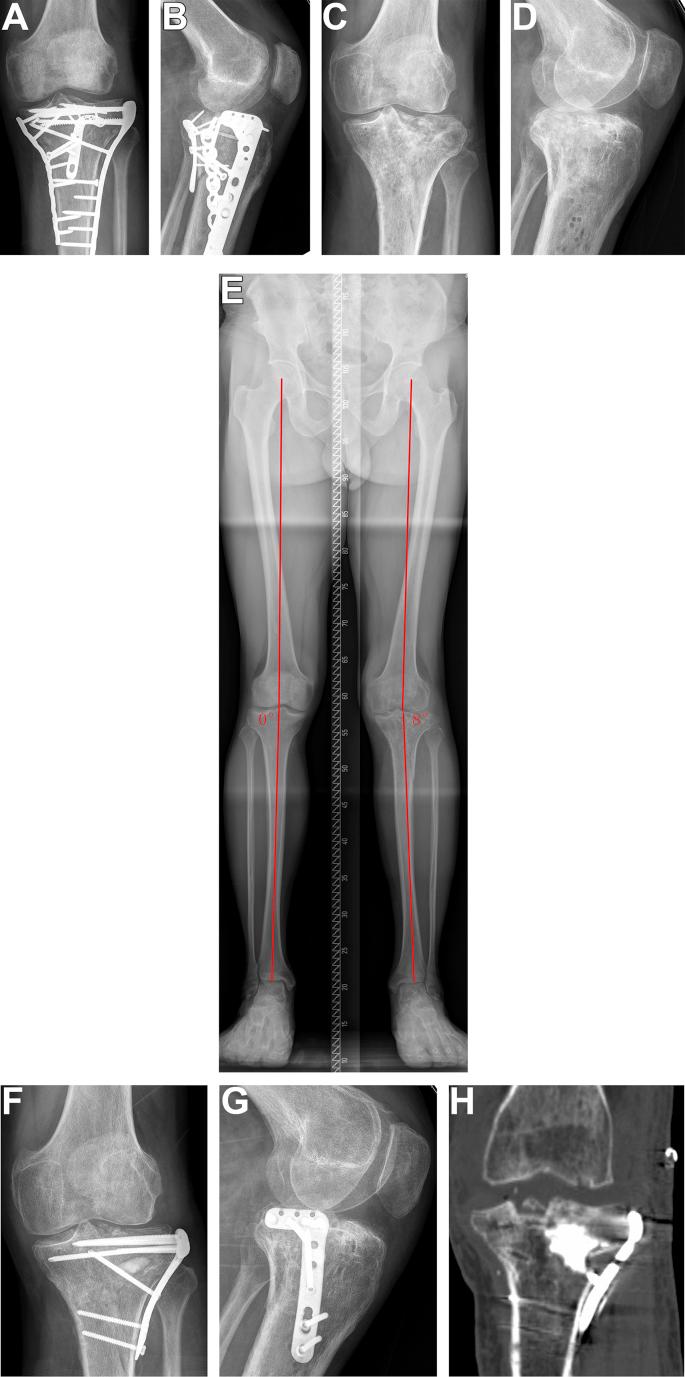

The aim of this study was to evaluate our treatment algorithm and results in revision surgery of malunited tibial plateau fracture after failure of initial treatment.

Our revision strategy was as follows: First, we determined the presence of any infection. Second, we determined whether the patient required total knee arthroplasty (TKA). Third, based on the characteristics of the tibial plateau fracture malunion, patients underwent one of the following surgical methods to achieve reduction: original fracture line osteotomy, tibial tubercle + original fracture line osteotomy, fibula head + original fracture line osteotomy, and metaphyseal open window reduction rod technique. The results was assessed with healing time, Rasmussen score, knee range of motion and complication rates.

A total of 25 patients 16 men and 9 women; Mean age: 47.4 years (range: 35-63 years) underwent tibial plateau fracture revision operation. The time interval between the two surgeries was 2-24 months. The follow-up time was 12-30 months, and the operation time was 120-300 min. All patients received bone union at the last follow-up. The healing time was 3-6 months. The postoperative Rasmussen score was 19-29 (mean 23.8) compared with 14.4 points before the operation (p < 0.05). The postoperative knee joint activity was 60-110° (mean 95.0°), compared with 57.8° before the operation (p < 0.05). Six patients still had a 2-mm collapse on the articular surface, and 4 patients still had slight valgus (<5°). Except for 2 TKA cases, fracture reduction was excellent in 15 cases and good in 8 cases, with a good rate of 100%. Superficial wound infections occurred in 3 patients.

Because revision of tibial plateau fracture malunion caused by failure of initial treatment is difficult, it is necessary to create a detailed surgical plan before the operation. Satisfactory clinical effects can be obtained if the correct revision strategy is used. The key to success is adopting a proper revision strategy according to the unique characteristics of the patient's tibial plateau fracture malunion.